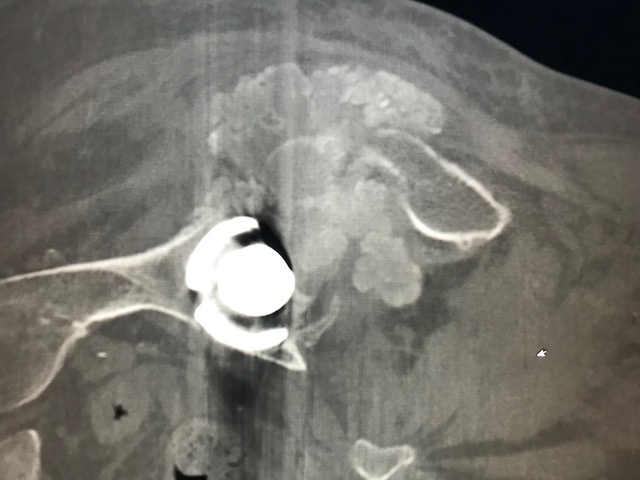

Figure 2 for case Tumoral calcinosis ( RID5202 )

Figure 2